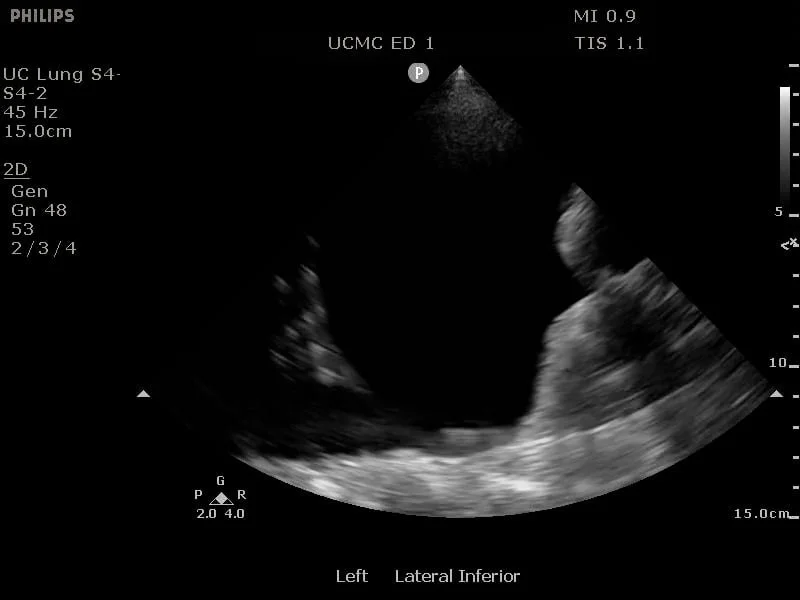

Confirm the extent of the pleural effusion using bedside ultrasound which reduces the risk of pneumothorax and increases the success rate. A curvilinear probe is the optimal choice for this procedure and placed on the patient’s back or axilla in the sagittal position (8). The lung is echogenic and moves with respiration. Find the deepest fluid pocket superficial to the lung.